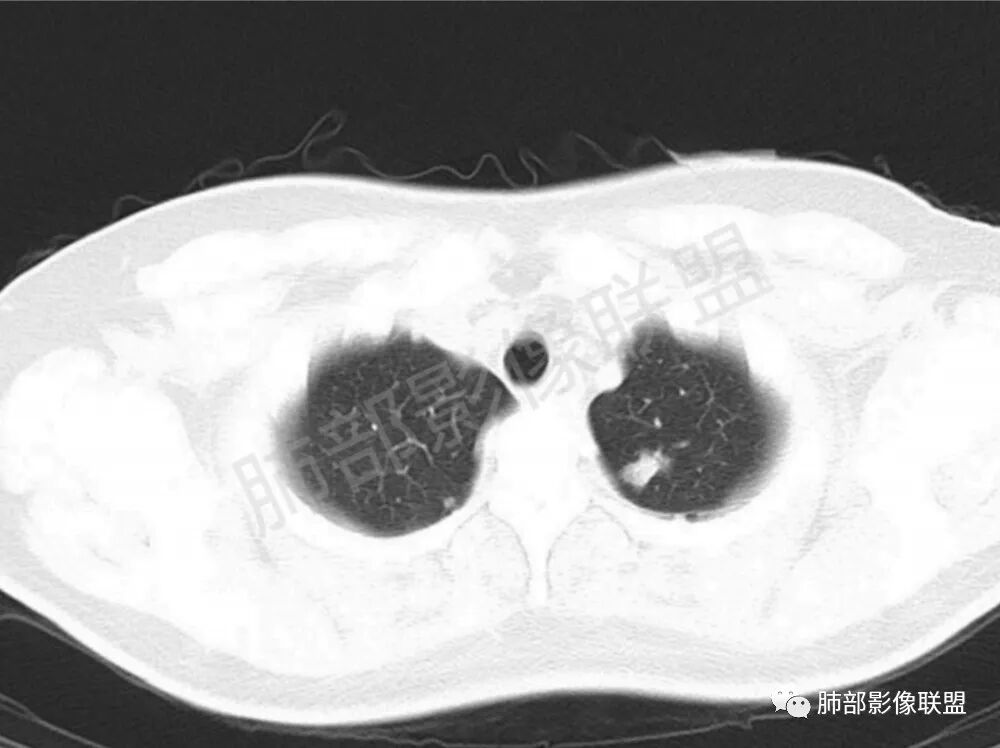

男性,22岁,HIV病史,症状半年,双肺多发大小不等结节影,边缘光滑,密度均匀,以胸膜下分布为主,部分与胸膜相连,胸膜下脂肪间隙可见,病灶近段支气管走行病灶内,远端似有堵塞,无增强图像,考虑隐球菌,鉴别:淋巴瘤,GPA

双肺多发结节影,膨隆,边缘光滑,圆顿,沿支气管血管束分布为主,部分贴胸膜,部分见空洞,空气支气管征

两肺多发结节性,大部分位于胸膜下,部分结节周围可见晕征。局部结节内可见扩张的支气管,纵隔淋巴结大,脾大,22岁男,HIV阳性,常规先考虑隐球菌。鉴别淋巴瘤,结核,马儿。

男,22,半年前咳嗽伴少痰,查HIV阳性,痰查TB阳性,既往有肺部斑片影伴空洞、纵隔淋巴结肿大、脾大。SCC、CA50、CA199、FER增高,此次胸部CT:两肺多发结节影,部分沿血管束分布,部分贴胸膜下,大小不一,密度不一,部分较散、边缘模糊,部分较实、圆钝、周围模糊晕,部分结节有支气管进入穿行自然,部分结节有血管分支自如通过。考虑HI∨相关淋巴增殖类病变,淋巴瘤?LYG?鉴别PC、TB。

1.双肺多发大小不一结节,外围为主,边界尚清,部分周围似有GGO

2.类圆形,部分与胸膜相连,糊墙

3.支气管通畅或近端堵塞